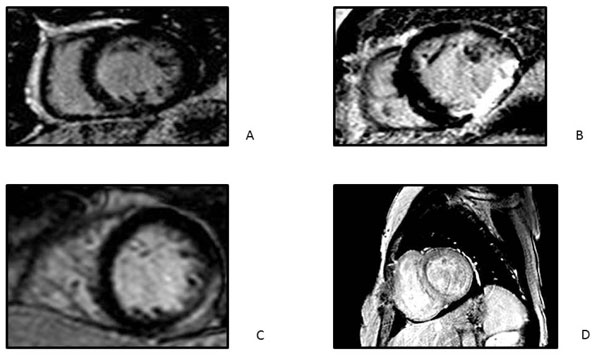

La caracterización tisular de la CR y la evaluación del patrón de fibrosis y su ubicación, mediante la secuencia de realce tardío, pueden ser útiles ante la sospecha de enfermedades infiltrativas o inflamatorias (Figura 3).

Figura 3: Patrones de realce tardío en búsqueda etiológica. A: normal. B: tipo isquémico (subendocárdico o transmural); C: tipo no isquémico (paciente con miocarditis); D: patrón de realce tardío endocárdico global (paciente con amiloidosis cardíaca).